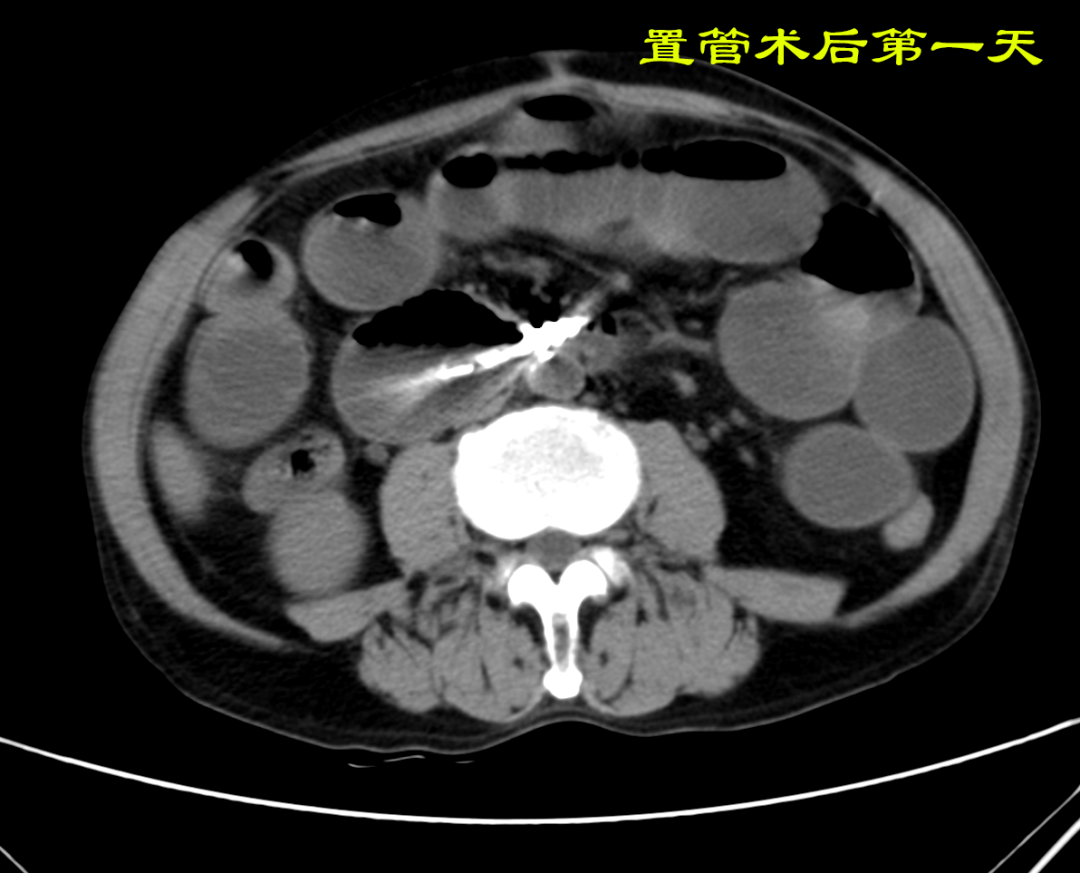

病例:患者男性,74岁,因“腹痛、腹胀伴呕吐、肛门停止排气排便20小时”于2021年7月24日入住我院普外科。患者1月前因回肠穿孔于我院普外科手术治疗,入院后明确诊断为术后粘连性小肠梗阻,经胃管引流等保守治疗无好转。因患者有严重心肺疾患,再次手术风险较大,并且术后再发粘连性肠梗阻的可能性也很大。经过与患者家属沟通后,最后决定采用胃镜引导下置入经鼻插入型肠梗阻导管技术来治疗肠梗阻。由我院消化内科副主任医师杨开余完成操作,耗时大约40分钟,患者术后第5天开始排气排便,腹痛、腹胀症状迅速消失,术后第7天拔除肠梗阻导管,恢复饮食。拔管至今已10天,患者已出院。随访患者无腹痛、腹胀,排便正常。

良好的引流是治疗肠梗阻的基本措施,低位小肠梗阻置入胃管引流常难以奏效,以往大多需要再次手术,而再次手术后粘连的几率高达70%。经鼻插入型肠梗阻导管就是将一根3米多长,内有四个腔道的管道置入十二指肠后,在重力和肠道蠕动的作用下,导管先端部将自动向前运动,直至到达梗阻部位。在导管到达梗阻部位后,可进行双对比造影检查了解狭窄病因,也可以对狭窄处进行扩张,还可以作为支架起到肠排列的治疗效果。肠梗阻导管治疗小肠梗阻属于微创型手术,具有痛苦小、疗效好、费用低、预防再次粘连等优点。